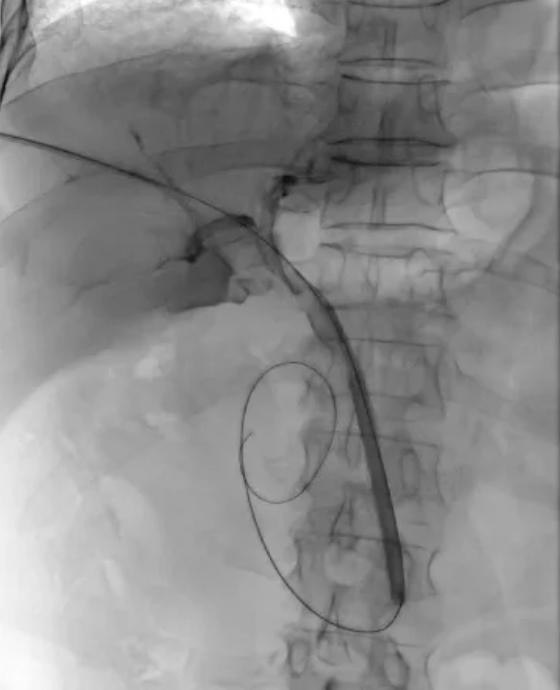

手术在局部麻醉下进行。在超声和X线透视的精准引导下,任虎虎副主任医师团队通过一个仅几毫米的穿刺点,成功建立了经皮经肝至胆总管的微细通道。

核心步骤随之展开:一根在介入手术中极为常见的6F普通血管成形球囊,沿着通道被送至结石下方。连接压力泵,球囊缓缓张开,形成一个柔和的“推力面”。在透视屏幕的监视下,医生如同一位沉稳的“推手”,运用巧劲,稳健地将这颗困扰多日的结石,轻轻地“推”过了Oddi括约肌,进入了宽阔的十二指肠。